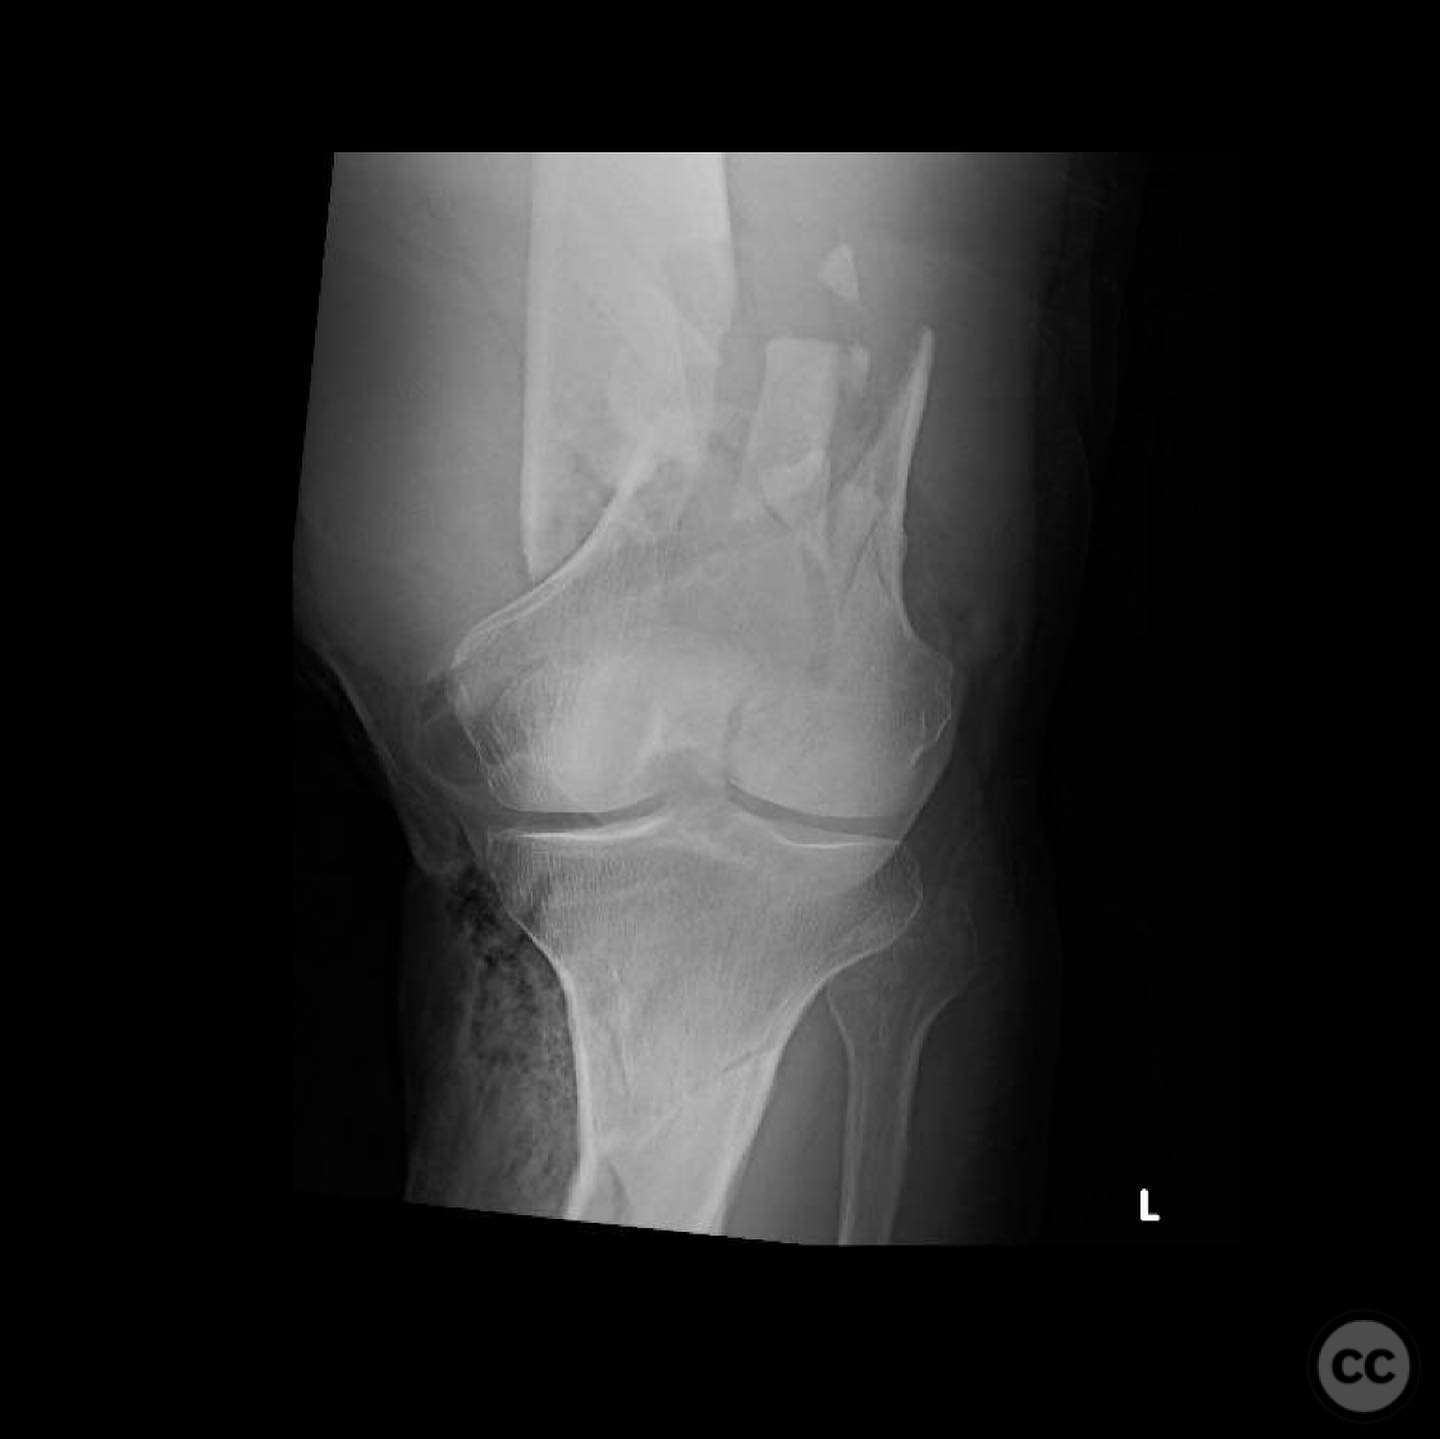

Clinical and radiological findings:  A 44-year-old male cyclist was involved in a collision with a car, resulting in open fractures of the distal femur and segmental tibia. The femoral fracture presented with a 4 cm transverse wound on the anterior aspect, while the tibial fracture had a 2 cm anterolateral wound at the distal site. There were no associated head, chest, or abdominal injuries, and compartment syndrome was not present. Vascular examination was unremarkable.

Planning remarks:  The preoperative plan involved initial debridement and irrigation of both open fractures. The tibia was prioritized for intramedullary nailing, followed by spanning external fixation of the distal femur. Definitive fixation of the distal femur was planned for two days post-initial stabilization.

The tibial nailing required precise identification of the start site under fluoroscopic guidance, with percutaneous clamps aiding in reduction. Blocking screws were considered but not necessary due to successful reduction with clamps alone. The distal femur presented challenges in achieving coronal and sagittal alignment, necessitating reliance on the external fixator for reduction before proceeding with plating.